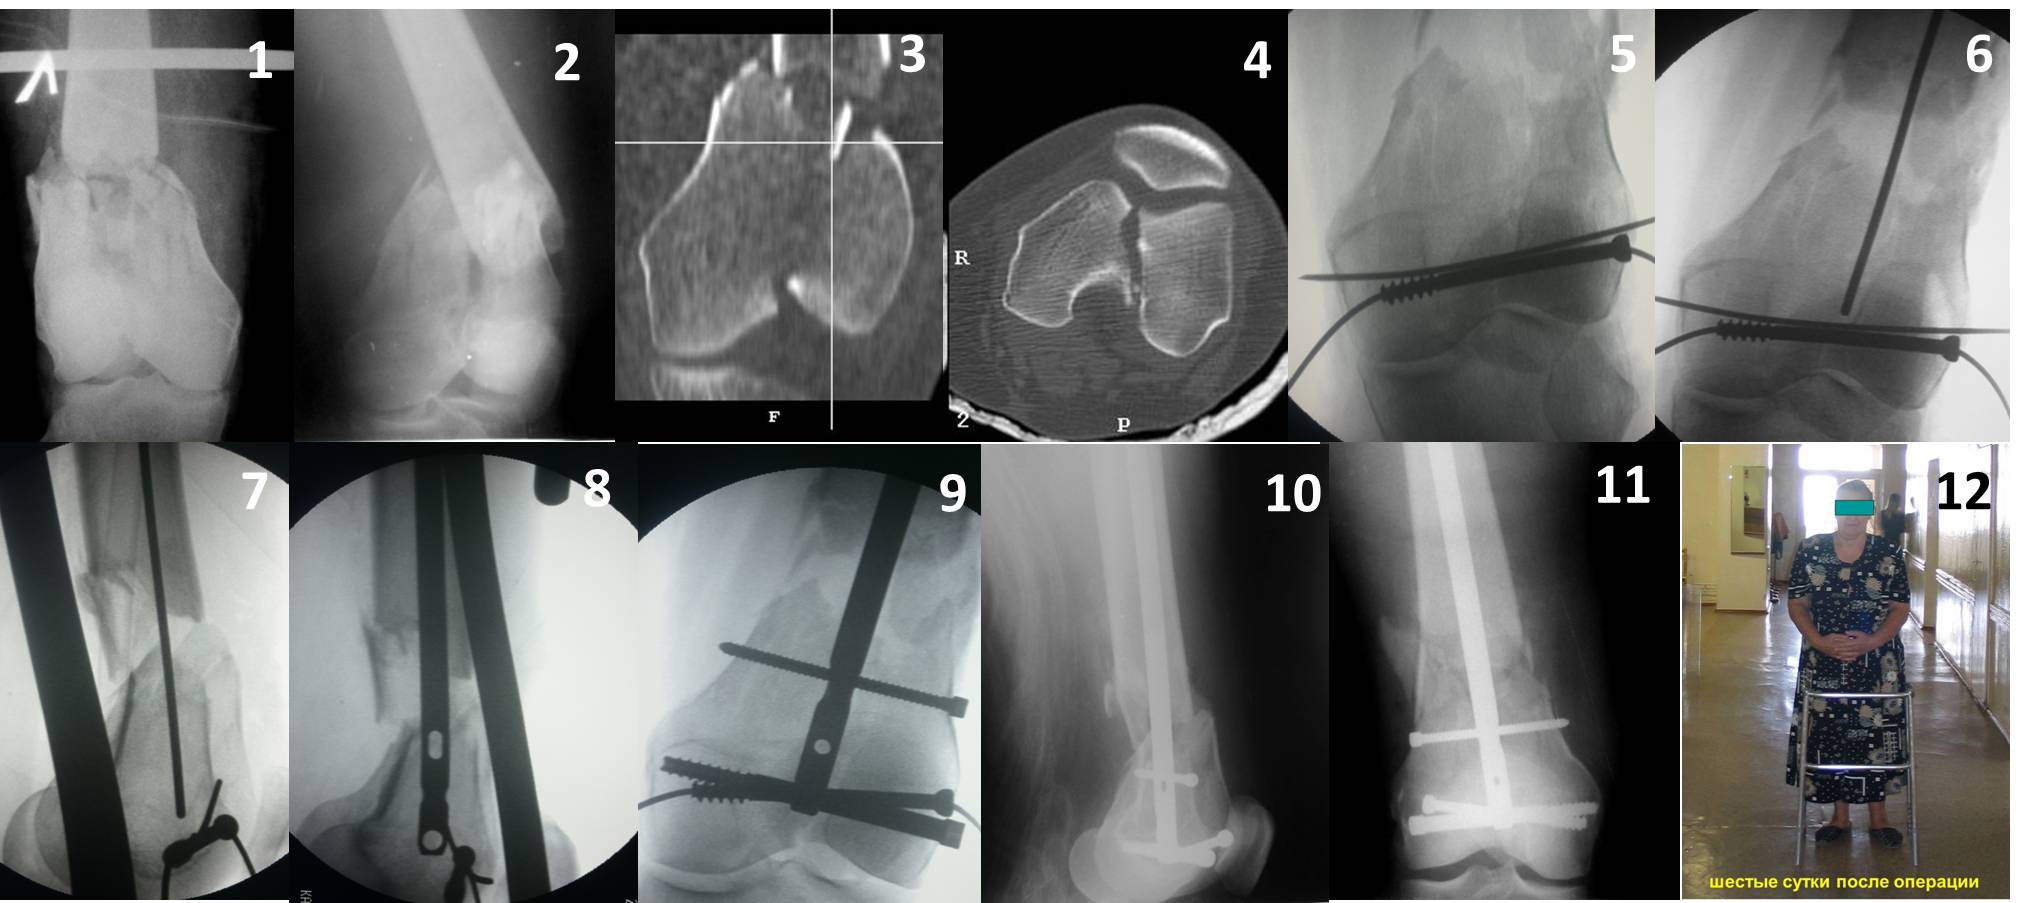

Ответ на эту часть Вашего поста – вложенный файл. Больная оперирована неделю назад по поводу открытого перелома дистального эпиметафиза бедренной кости. После операции она идёт в рентгенкабинет для выполнения послеоперационной контрольной рентгенографии, представленной на слайдах 10 и 11. Узнав, почему её фотографируют, просила передать Вам, Антон, привет.

Антеградное штифтование не очень годится при переломах типа C3, когда есть многооскольчатость именно суставной поверхности. А при переломах типа C1 и С2, т.е. и в обсуждаемом случае тоже, он как раз вполне оптимален. На межфрагментарную компрессию как-то не приходилось так драматически полагаться при интрамедуллярном остеосинтезе, результаты хорошие без нее были.

В этой терминологии мы, получается, создавали компрессию встречными спицами с упорами или reduction clamps, а потом вполне обходились запирающими винтами как позиционными. Бывает, проводим 1-2 спонгиозных винта 6,5-8 мм - вот они вполне компрессирующие.

И уже лет шесть мы используем возможность ввести в дистальное овальное отверстие 3 винта, которые именно запираются в этом отверстии, не люфтят, а обеспечивают угловую стабильность - см картинку.

Получается и стабильно, и очень дистально, нижний край отверстия в 3 мм от дистального конца гвоздя.

В приложении пример недавней операции, C3, открытая репозиция, фиксация мыщелков спицами и винтами, ретроградный синтез большеберцовым гвоздем 10,5 мм диаметром, винты 5 мм.

Позволю себе напомнить коллегам ещё раз, что являюсь сторонником антеградного остеосинтеза при переломах дистального эпиметафиза бедренной кости. Такая приверженность основана не на преимуществах внесуставного введения стержня или большем проценте положительных результатов. Она основана на возможности обеспечить блокирование на минимальном расстоянии от суставной поверхности в нескомпрометированной кости и, таким образом стабилизировать максимально низкие переломы. В приведенном Вами случае самый дистальный из блокирующих винтов проведен на расстоянии более 2 см от конца стержня. Из-за того, что к стержню присоединяется кондуктор, на стержне теряется 1-1,5 см его длины, где можно было разместить отверстия для блокирования. И что более важно, вместе с потерянной для этой цели длиной стержня утрачивается для размещения блокировочных винтов, пожалуй, самая ценная часть дистального эпиметафиза бедренной кости. Проблемы дистального блокирования в разных плоскостях, локализации точки ввода стержня при антеградном остеосинтезе – это всё решаемые технические проблемы. Но антеградный остеосинтез низких дистальных переломов бедра при адекватном блокировании в нескомпрометированной кости обеспечивает решение стратегической задачи – стабильный остеосинтез и возможность нагрузки.